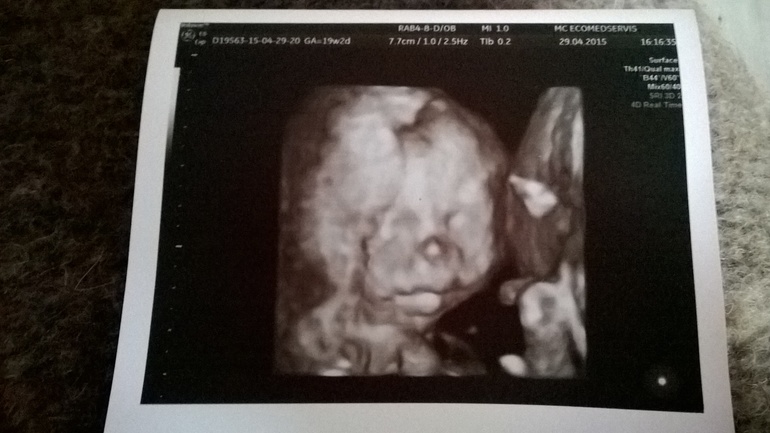

Фотопуз:

Детеныш: с 21 апреля активно общается со мной и папой ( остальных пока боится). До этого были непонятные «бульканья», а сейчас уже ни с чем не спутаешь )) Особенно активный вечером и в обед.

А вот наш Максим Дмитриевич (пока так. Как родится - посмотрим как лучше назвать )